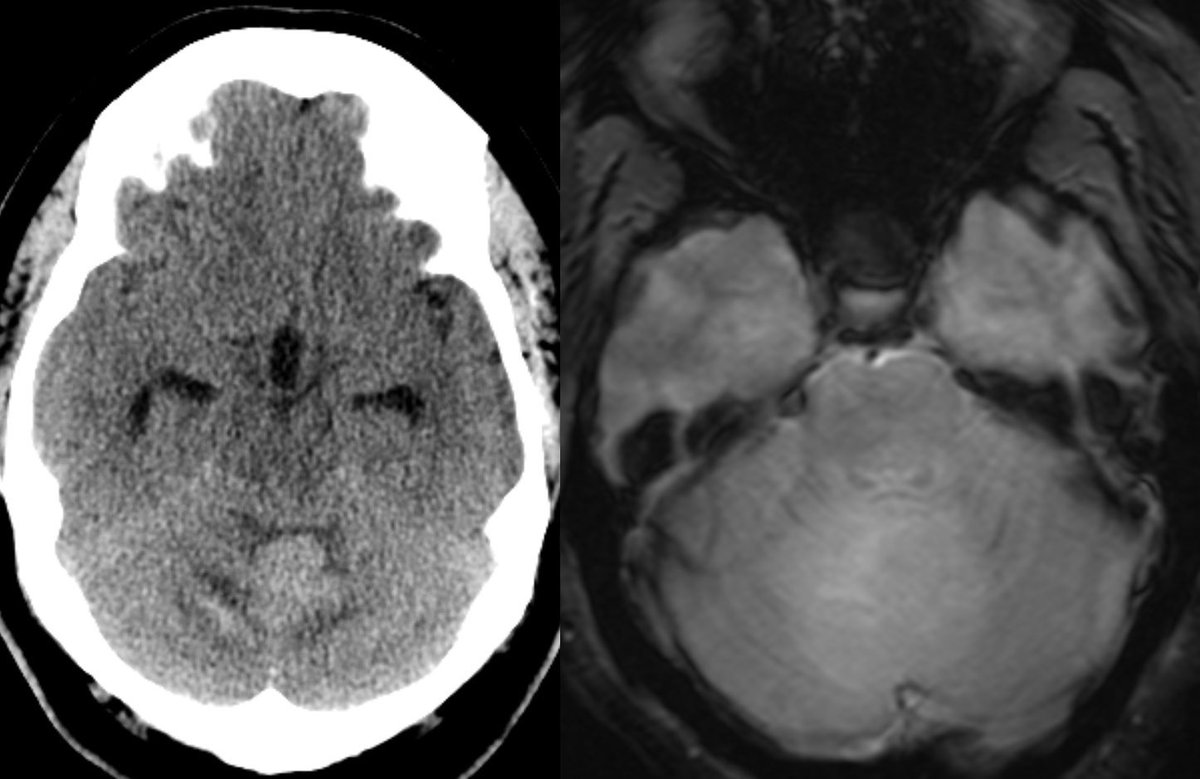

⭐️ Companion case of Lhermitte-Duclos - Unilateral cerebellar mass w/ striations due to hyperintense expanded fovea on T2 w/ normal signal intervening parenchyma

Typically there is no to little enhancement and high signal on DWI due to T2 shine-through w/ high signal on ADC x.com

💡 Both Lhermitte-Duclos & Medulloblastoma SHH can have a striated appearance! Use DWI/ADC, density on CT, & enhancement to distinguish!

🔷Location: Most commonly LATERALLY IN THE CEREBELLAR HEMISPHERES (~62%)

💡 Hypercellular tumor so DENSE on CT and DIFFUSION RESTRICTION (consistent feature)

▶️Round/lobulated morphology